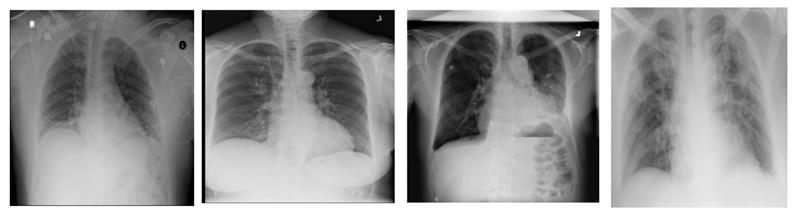

Figure 11

Heatmap of X-ray images with (from left-to-right) Edema, Effusion, Emphysema, COVID findings.

4.1 Comparative Analysis

As we have already discussed in Section 1, that there is not much work present which targeted all 14 types of chest diseases plus COVID-19 caused pneumonia. Although, three papers performed such experiments one of them contributed in terms of data, second provided results with 15 classes but with highly normalized data and 3rd provided reasonable accuracy but still used normalized data. Table 2 provides comparative analysis of training and validation in terms of accuracy. It shows that the validation accuracy increases from around 66% to around 81%. However, with more training data with balanced classes, the model accuracy can increase significantly. The sample of heat-maps of GAN generated data can be visualized in the Figure 11.